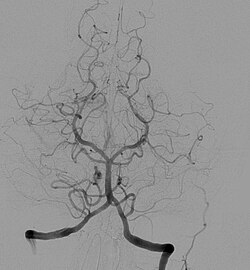

Jod kao teški element je pogodan za radiloško snimanje, jer radi sjene (kontrast) na snimkama kod računalne tomografije i angiografije. Angiološki pregledi predstavljaju kontrastne invazivne dijagnostičke radiološke metode pregleda srca i krvnih žila. Indikacije za te preglede predstavljaju bolesti krvožilnog sustava, centralnog živčanog sustava, sredoprsja i pluća, trbušnih organa i urogenitalnih organa. Oni su postali nezamjenjive u dijagnostici kongenitalnih vaskularnih malformacija, ateromatoze, tromboze i embolije te u dijagnostici tumora i oboljenja parenhimnih organa. Može se reći da je arteriografija znatno pridonijela napretku medicine uopće. Kontraindikacije za tu vrstu dijagnostike jesu opće loše stanje pacijenta, produženo vrijeme krvarenja, smanjen broj trombocita, kao i dokazana alergija na jod, koji je sastavni dio kontrastnog sredstva.